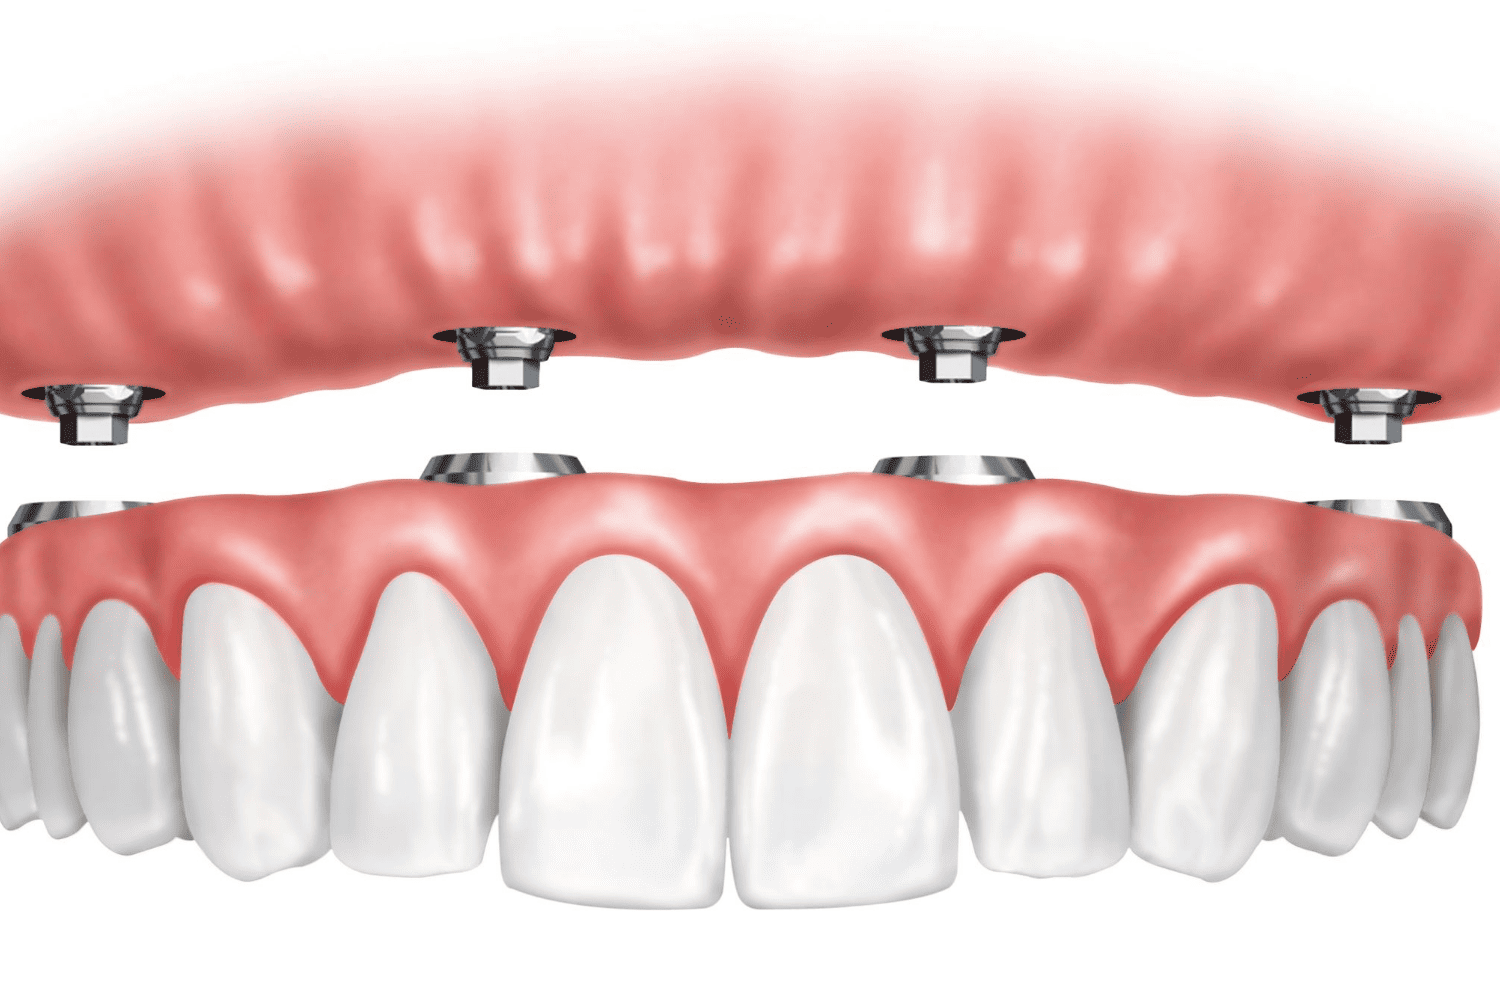

READ MOREHybrid Dentures in Jaipur Services Crowns Bridges Dentures...